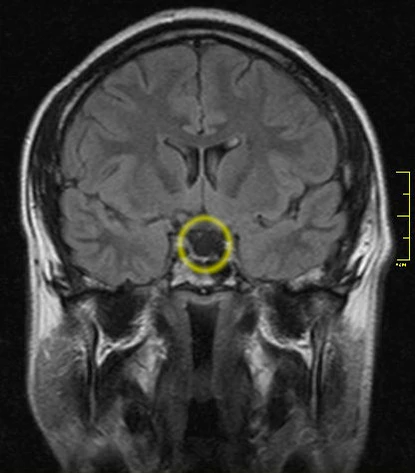

Диагностика

В типичных случаях диагностика проста́. Своевременная диагностика задерживается у пациентов с вялотекущим синдромом Шихана, хотя отсутствие лактации после родов, сопровождавшихся геморрагией, длительное снижение трудоспособности и нарушения менструальной функции должны наводить на мысль о гипопитуитаризме[2].